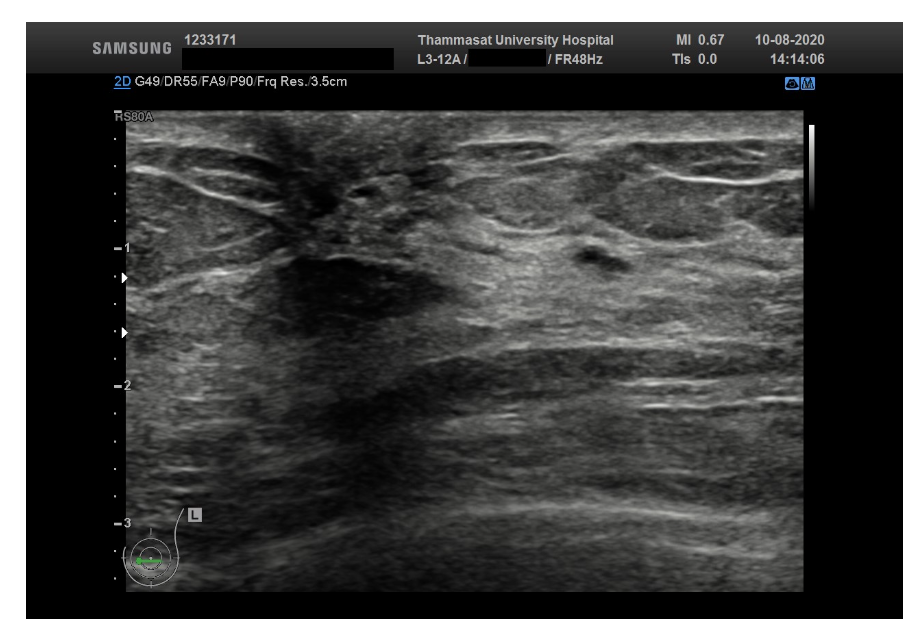

The third dataset is Thammasat University dataset, which consists of 500 breast ultrasound images, however, every image doesn’t have a mask.